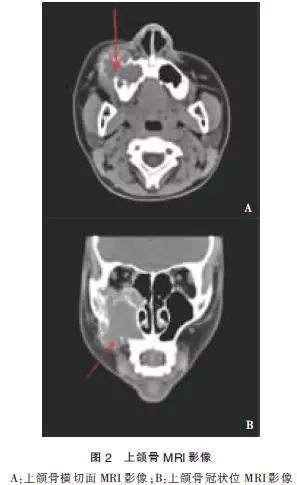

患者于2014-03-14行MRI檢查示:右側(cè)上頜竇為中心,右側(cè)眶下壁至上頜骨區(qū)頜面部可見一不規(guī)則形軟組織信號腫塊影,大小約4.2 cm×4.7cm×5.9cm。輪廓不光整,病灶可見斑點(diǎn)狀,棒狀短T1高信號,短T2低信號影,輪廓清晰。病灶部分突入右側(cè)鼻腔內(nèi),鼻中隔居中,注射造影劑后上述病灶呈不均勻顯著異常強(qiáng)化,右側(cè)額竇、篩竇及蝶竇內(nèi)可見長T2高信號影。

影像學(xué)診斷:①右側(cè)頜面部占位,血管瘤或惡性腫瘤可能;②垂體形態(tài)不規(guī)則,請結(jié)合臨床考慮(圖2)。于2014-03-18行“頸內(nèi)外動脈造影+血管瘤供血動脈栓塞術(shù)”,患者仰臥,心電監(jiān)護(hù)下,常規(guī)右腹股溝消毒,鋪無菌巾,2%利多卡因局麻后,以技術(shù)穿刺右股動脈,置入5F鞘管送5F單彎導(dǎo)管分別選擇性進(jìn)入兩側(cè)頸動脈。右側(cè)頸內(nèi)外動脈造影(圖3):右側(cè)頜面部可見富血供染色病灶,呈現(xiàn)“血管湖”徑,右側(cè)頜內(nèi)動脈為主要供血動脈,參與約80%供血,右側(cè)面動脈及顳淺動脈分支參與約10%供血,右側(cè)眼動脈分支參與約10%供血,左側(cè)頸內(nèi)動脈及各大腦動脈及其分支顯影清晰,未見明顯異常。